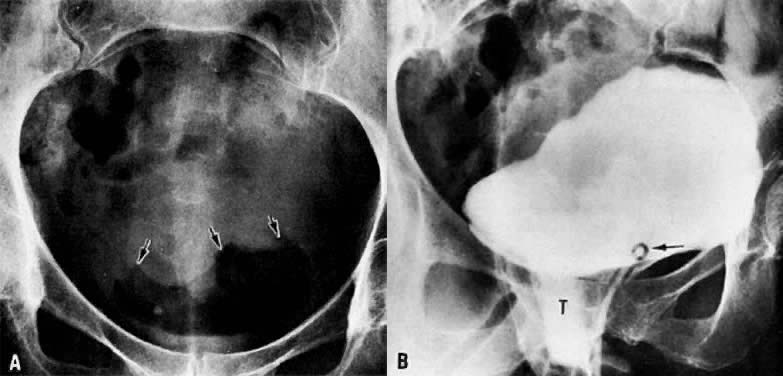

A. Plain film of abdomen. Air-filled bladder in a patient with vesicovaginal fistula. Dome of bladder is outlined with arrows. B. Cystogram. Contrast medium fills the bladder and runs onto the vaginal tampon (T) inferior to the bladder and posterior to the Foley catheter (arrow).